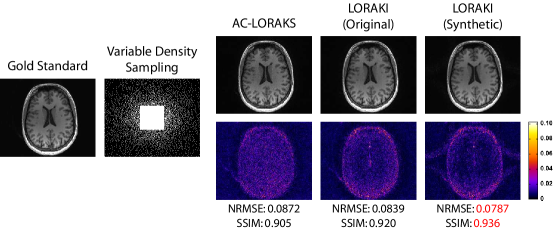

Figureย 2, Tableย 1, and supporting Fig.ย S1 show results from reconstructing uniformly-undersampled T2-weighted data. In this specific case, we simulated an acquisition that measured every fourth line of k-space, while also fully-acquiring the central 32 phase encoding lines to be used as ACS data. Taken together, this results in an effective acceleration factor of 2.6ร—2.6\times. As can be observed from Fig.ย 2 and Tableย 1, the proposed LORAKI approach had the best performance in all cases, with uniformly lower NRMSE values and uniformly higher SSIM values compared to GRAPPA, RAKI, or AC-LORAKS. We observed similar NRMSE and SSIM values for LORAKI when using the original ACS data or when using synthetic ACS data generated from an initial AC-LORAKS reconstruction of the data. In this specific case, the amount of acquired ACS data is already relatively high, which may explain the relative lack of impact from using synthetic ACS data. A corresponding ESP plot shown in supporting Fig.ย S1 shows that LORAKI approaches have consistently similar or better error characteristics than other methods across all spatial frequencies, with the most significant advantage at high-spatial frequencies.

Figure 2: Representative reconstruction results for uniformly-undersampled T2-weighted data. The top row shows reconstructed images for one slice in a linear grayscale, where the gold standard image has been normalized to range from 0 (black) to 1 (white). The bottom row shows error images with the indicated colorscale. NRMSE and SSIM values are also shown below each image, with the best values highlighted in red.

Table 1: Quantitative reconstruction performance metrics for 5 different slices of the T2-weighted dataset, using the same sampling pattern shown in Fig.ย 2. The best performance metrics are highlighted in red.